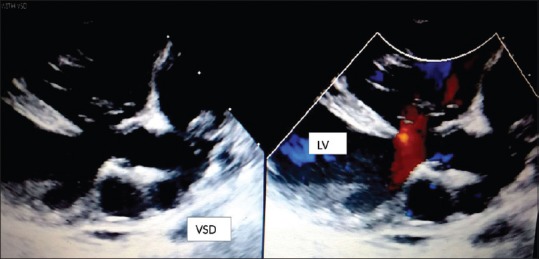

Chest X-ray showed cardiomegaly with a left ventricle (LV) type apex and pulmonary venous congestion [Figure 1]. Electrocardiogram showed sinus tachycardia with nonspecific ST depression in precordial leads [Figure 2]. Echo was done at the bedside which showed biventricular dysfunction with LV ejection fraction of 25% (severe dysfunction), moderate mitral regurgitation, and a slightly malaligned large subaortic VSD [Figures 3 and 4]. Laboratory investigations showed normal hemogram, but erythrocyte sedimentation rate and C-reactive protein were high. Renal parameters were deranged while creatine kinase MB and liver enzymes were elevated [Table 1]. Ultrasound for the kidneys was normal.

Figure 3.

Parasternal long axis view showing malaligned large subaortic ventricular septal defect shunting left to right and a dilated left ventricle